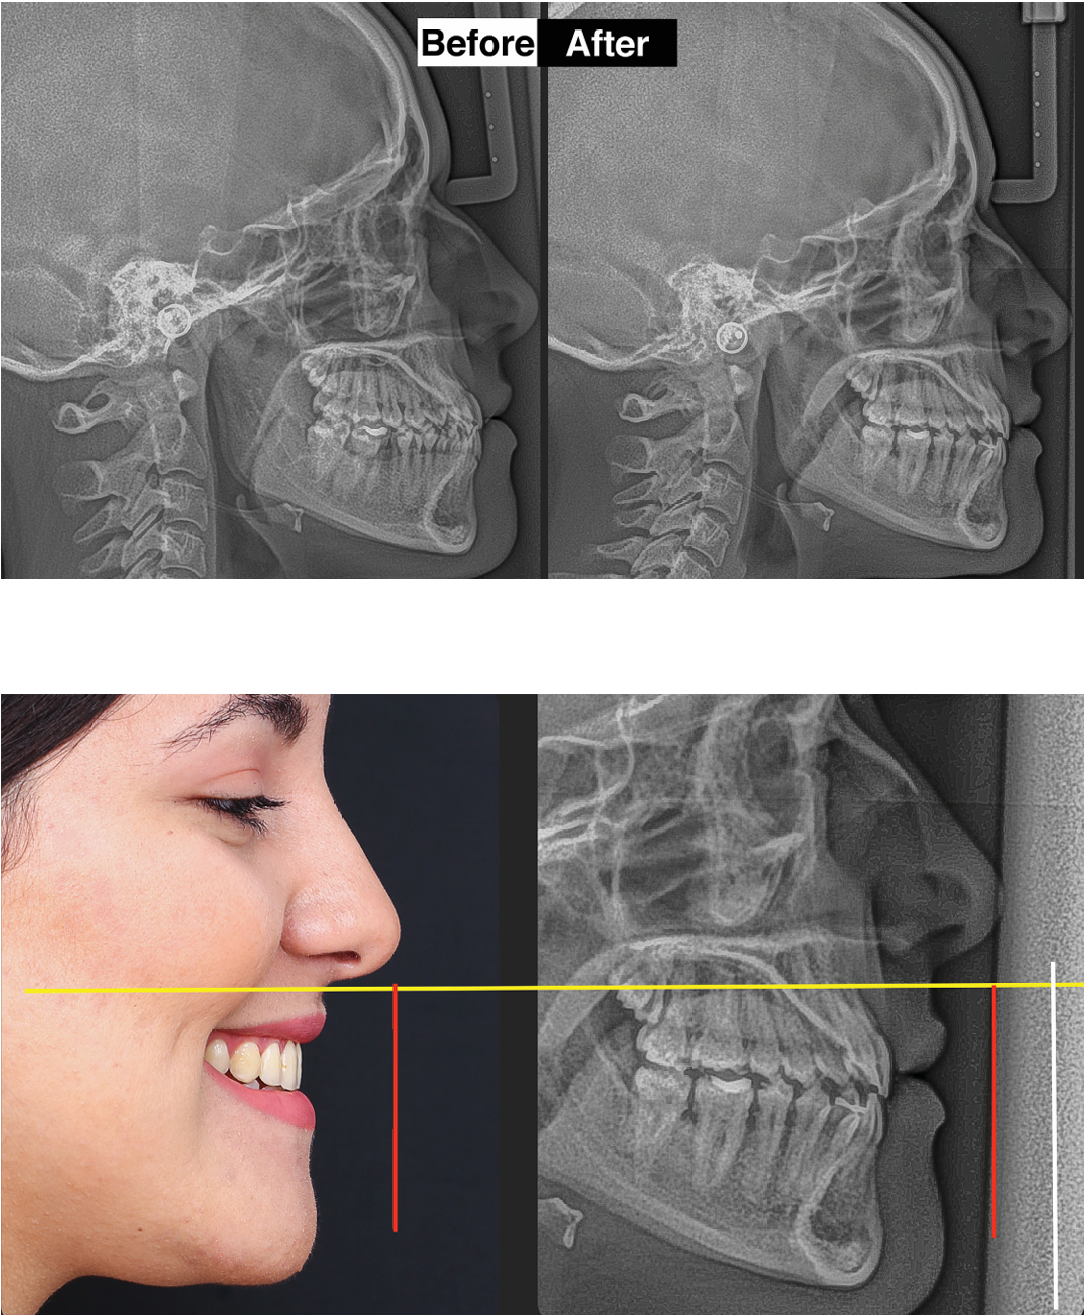

Pacjent 4, Dr Pitts Protocol, 14 miesięcy